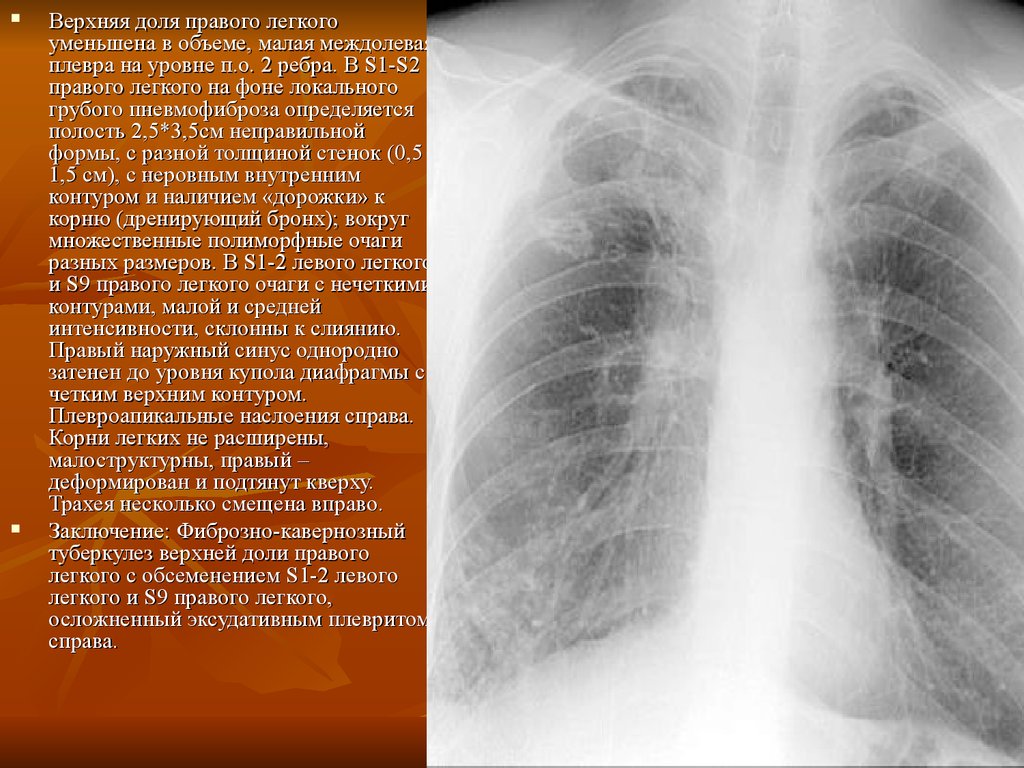

Диагностика плеврального выпота: что нужно знать